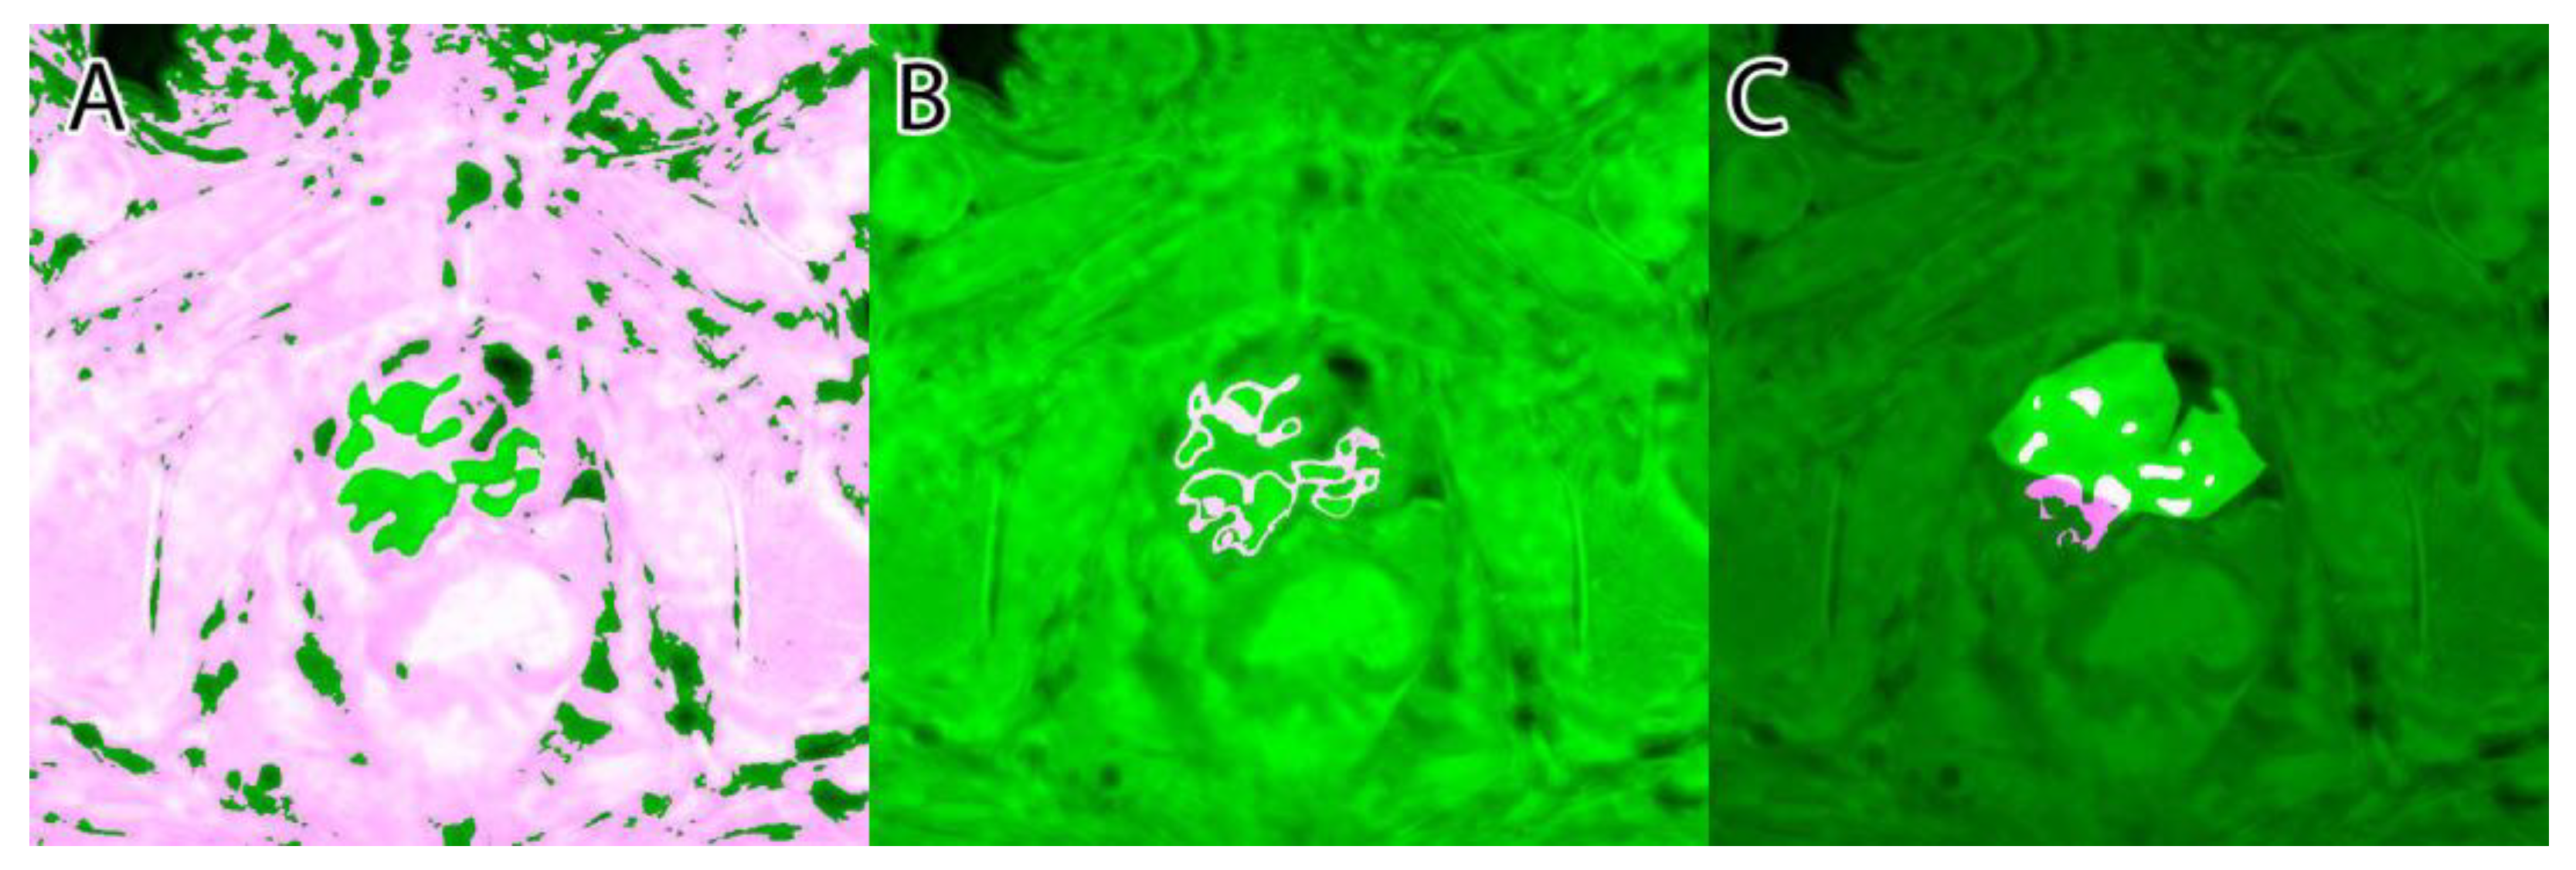

Their overlapping segmentation of PI-RADS 3, PI-RADS 4, and PI-RADS 5 lesions were considered as ground truth, as seen in Figure 4.

A sample of the ground truth marking can be seen in Figure 4.

Figure 4. Ground truth: (A)—PI-RADS 3; (B)—PI-RADS 4; (C)—PI-RADS 5; (D)—extraprostatic invasion.